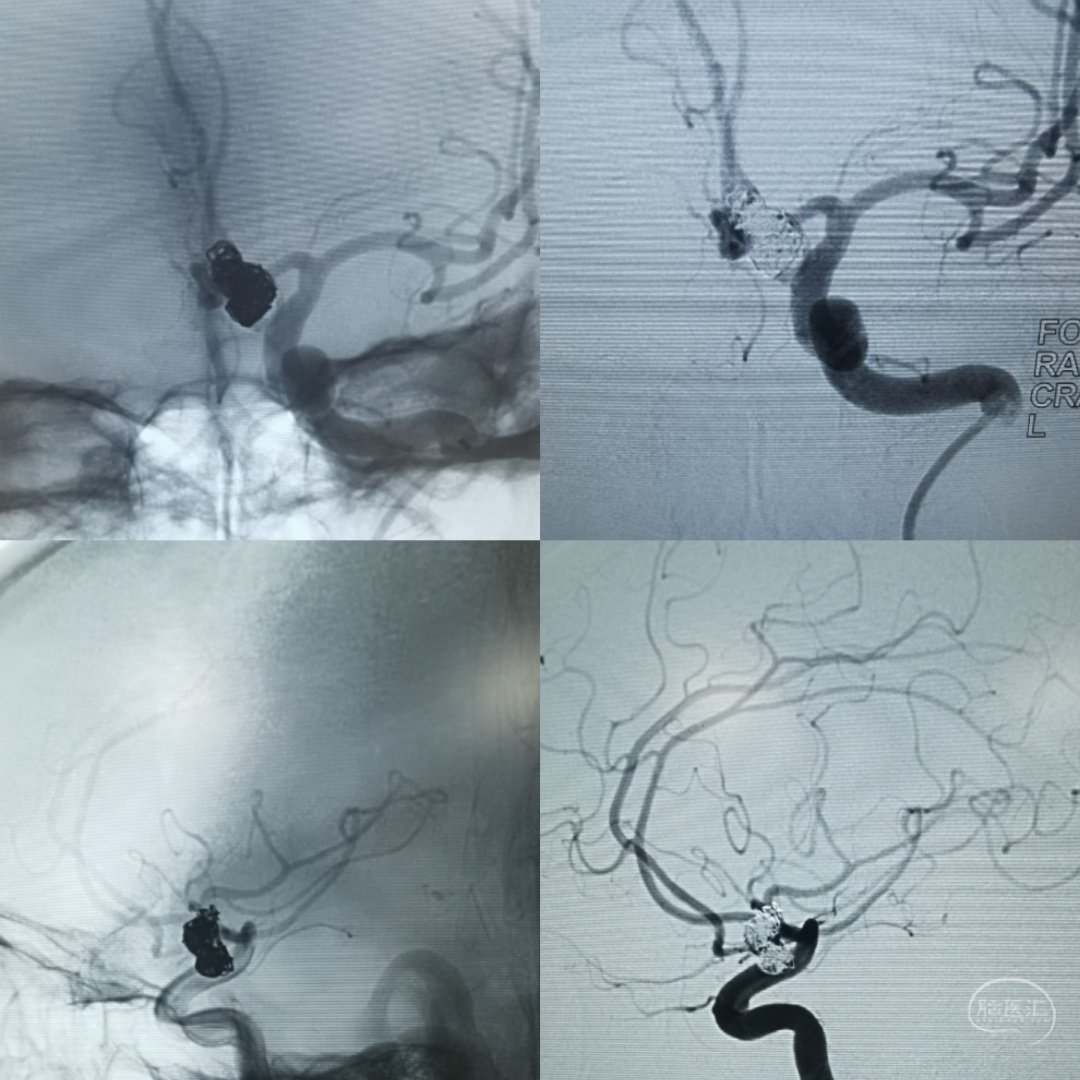

左侧颈内动脉造影正位片和侧位片,可见前交通部位大型动脉瘤,动脉瘤颈显示不清楚,左侧大脑前动脉a1段向双侧a2段供血。

左侧颈内动脉三维旋转造影可见动脉瘤位于前交通部位,累及双侧A2,形态呈长条分叶,顶端可见小子瘤。并可看到双侧a2近端血管痉挛表现

采用双微导管技术,其中一根为导管头端塑成S形,指向瘤体的上部,另外一根微导管塑成C形,指向瘤体的下端,同时,两根味道管经过留颈部,可以起到对瘤颈以及双侧A2的部分保护作用。弹簧圈填塞过程中应反复造影,确保双测A2血流通畅。

术后三维旋转造影可以看到动脉瘤不显影,双侧A2血流通畅,达到预期手术效果。